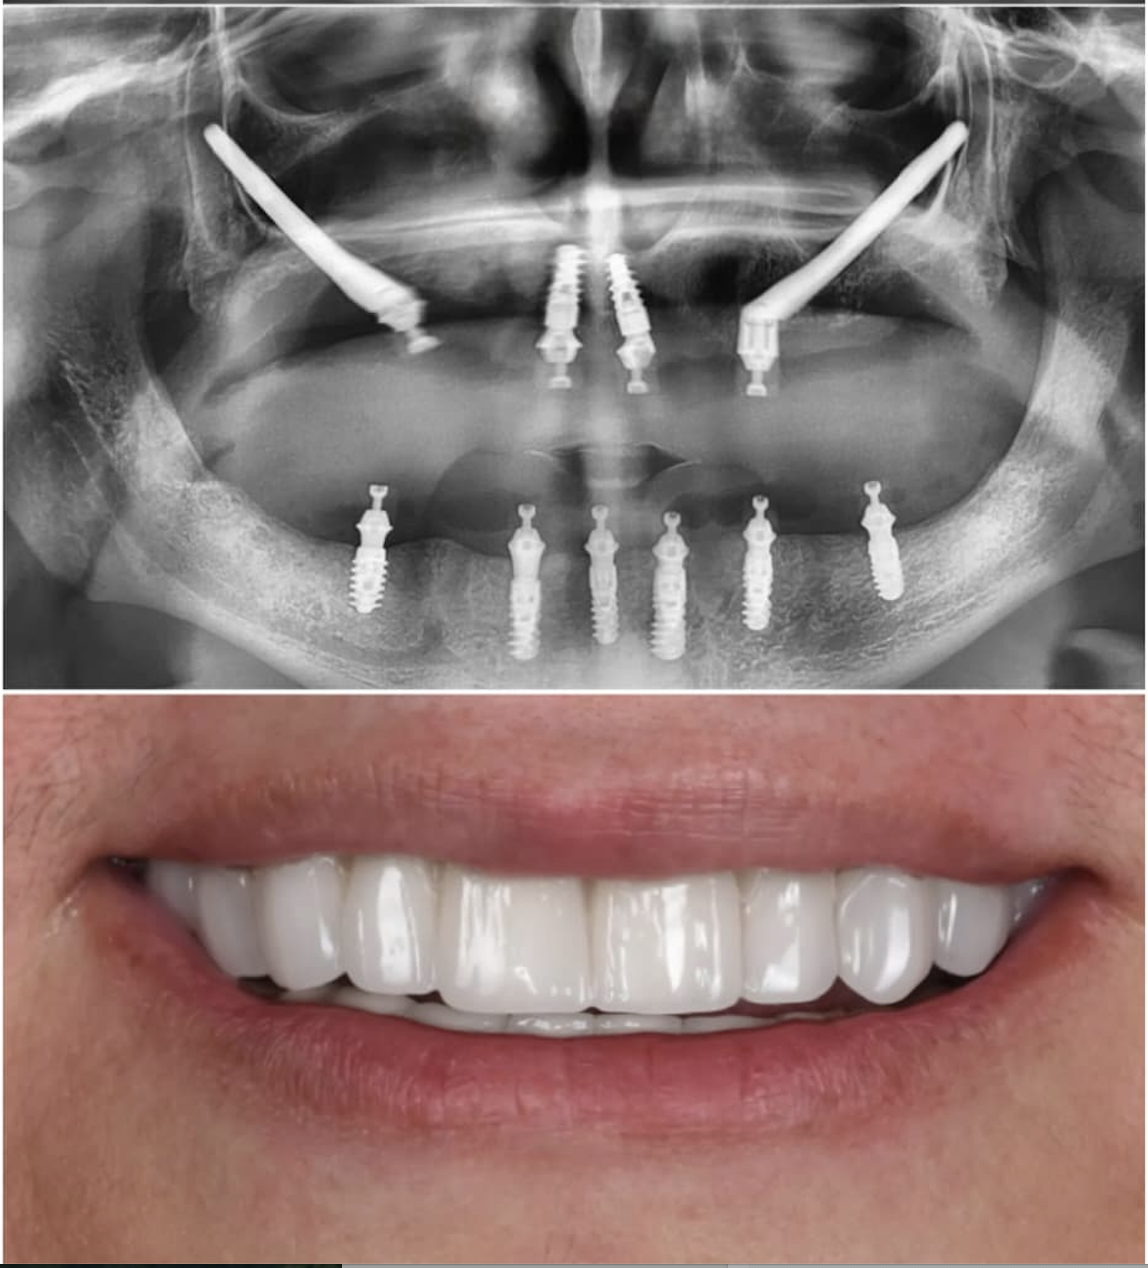

Immediate Loading Success

Before

Before treatment

After

After treatment